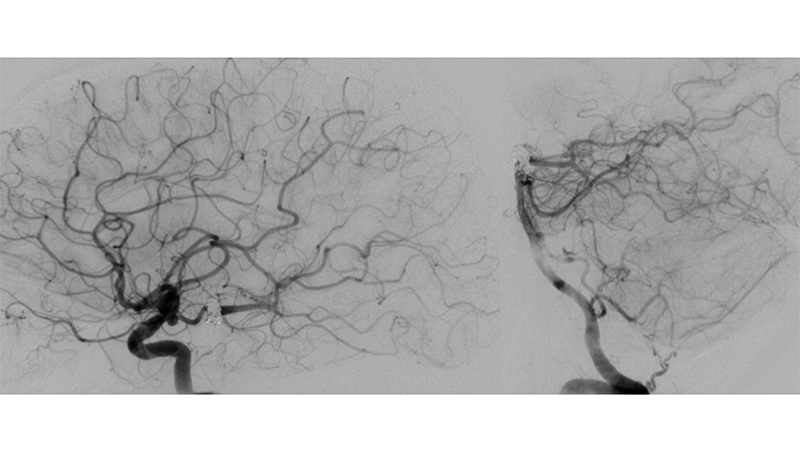

Εικόνα 5, 6: Πλήρης απόφραξη του ανευρύσματος με Y-stenting και coils, αμέσως μετά τον εμβολισμό.

Εικόνα 7, 8, 9: Πλήρης σταθερότητα του αποτελέσματος 2 χρόνια μετά, χωρίς εικόνα επανασηραγγοποίησης.